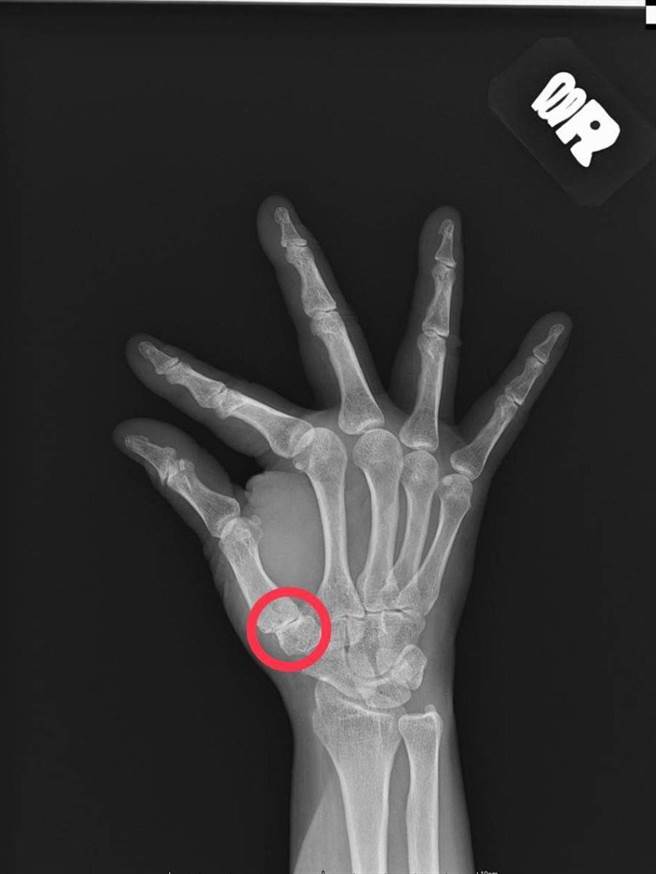

拇指的腕掌关节由许多腕骨掌骨形成关节面,提供了拇指极大的活动度及功能,但高活动度的关节若使用过度,常常使关节韧带受损及软骨磨损,进而造成骨刺与关节炎。(大里仁爱医院提供/潘虹恩台中传真)

大里仁爱医院骨科部长黄赞文说明,拇指的腕掌关节由许多腕骨掌骨形成关节面,提供了拇指极大的活动度及功能,包含伸、屈、抓、握、拿、捏等,但高活动度的关节若使用过度,常常使关节韧带受损及软骨磨损,进而造成骨刺与关节炎,令病人的日常生活困扰不已;拇指的腕掌关节炎原盛行于中老年的女性病患,近来有年轻化的趋势。

前台湾手外科医学会理事长、林口长庚医院运动医学科陈昭宇指出,针对严重拇指腕掌关节炎的手术方法可依照病患的需求选择客制化的手术方式。若病患为需要做粗重工作的年轻人,会比较适合採取拇指掌腕关节融合手术,术后较能保存抓握力量;一般民眾则是以腕骨切除合併肌腱转移与韧带重建手术为主。手术方式是使用微创手术将手腕里严重退化的大多角骨切除,再取病人前臂的掌长肌肌腱来转移重建韧带,提供关节在日常生活中活动的稳定。